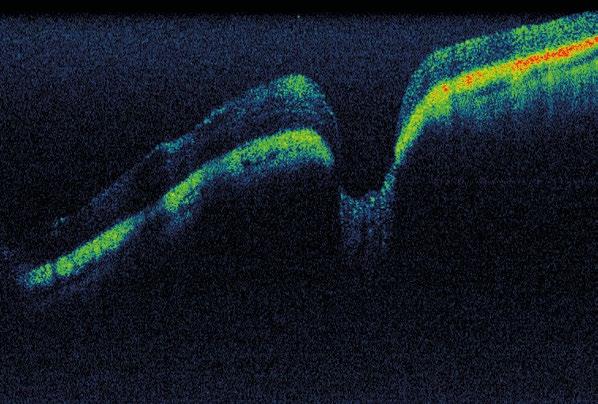

Tomografía de coherencia óptica